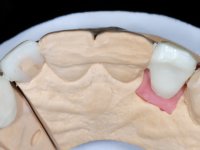

• Colocação de um Implante no local do dente 2.2. Reabilitação do implante com um “abutment” de componente coronário e gengival. em que o orifício de acesso ao parafuso fosse “camuflado” com uma faceta feldspática.

O tratamento iniciou-se com a re -preparação do coto do espigão falso coto fundido, com o objetivo de colocar as linhas de acabamento cervical com uma localização intra-sulcular e simultaneamente confecionar uma coroa provisória adaptada. Com um tratamento ortodôntico muito simples, fechou-se o diastema entre os incisivos centrais superiores e estabilizou-se esta posição com um arame colocado na superfície palatina dos centrais, funcionando como contenção. Posteriormente procurou-se fazer uma tração ortodôntica lenta do dente 2.2 com o intuito de diminuir, ainda que muito ligeiramente a perda óssea vertical nessa zona. Finalizada a tração, foi feita a extração do dente 2.2 e a zona foi reabilitada provisoriamente com uma coroa de resina composta colada aos dentes adjacentes. Foi colocado um implante dentário na zona do dente 2.2 sendo novamente colada a coroa provisória em resina, reabilitando provisoriamente a paciente durante o período de osseointegração. No dente 1.3 foi feita uma gengivectomia com bisturi elétrico, com a intenção de subir o nível cervical do 1.3 conseguindo uma maior harmonia com o dente 2.3. Estabilizados os tecidos moles, foi feita uma impressão com a técnica de moldeira aberta, utilizando silicones de adição de consistência “putty” e “light”. A recolha da cor, tanto da componente dentária como dos tecidos moles foi feita pelo ceramista no consultório.  No laboratório as impressões foram passadas a gesso e deram origem a modelos de trabalho que foram devidamente analisados. Foi decidido confecionar um “abutment” metalo-cerâmico aparafusado sobre o implante. Este “abutment” foi fundido com uma liga nobre e posteriormente revestido a cerâmica coronária e gengival. Dada a inclinação do implante o aparafusamento condicionou de forma inevitável a saída do orifício do parafuso pela superfície vestibular. No sentido de esconder esta situação, o desenho do “abutment” já foi idealizado com a intenção de acomodar na superfície vestibular a colagem de uma faceta feldspática. Este “abutment” foi provado em boca e foram feitos ajustes no componente cerâmico gengival. A sua adaptação aos tecidos moles foi feita tanto de forma subtrativa, com broca, como de forma aditiva, acrescentando resina composta de tonalidade gengival. Este acrescento de resina seria orientador do ceramista na colocação final da cerâmica de tonalidade gengival. A coroa que reabilitaria o dente 1.3 foi cimentada nesta consulta de prova com cimento de ionómero de vidro reforçado com resina composta. Finalizado o trabalho em laboratório da faceta sobre o 1.2 e o “abutment” e a faceta para o implante este foi colado em boca, após a colocação do isolamento absoluto. O trabalho satisfez plenamente a paciente. Durante oito anos a paciente foi seguida regularmente, mostrando-se agradada com o tratamento efetuado, no entanto começou a mostrar interesse em intervir esteticamente nos incisivos centrais superiores. Decidida a segunda fase da nossa intervenção, foi feita a preparação dentária dos dentes 1.1 e 2.1 para a colocação de duas facetas feldspáticas. Particular cuidado foi tido na preparação inter-proximal distal junto ao “abutment” do implante. Foi preciso avaliar muito pormenorizadamente o eixo de inserção da faceta em relação ao “abutment”. As facetas feldspáticas foram confecionadas em laboratório e posteriormente coladas em boca após a colocação de isolamento absoluto. Um ano após, iniciamos a nossa terceira fase de tratamento, após a faceta colada no dente 2.1 ter fraturado. A preparação dentária foi feita sobre a faceta colada, procurando estender mais para palatino o interface inter-proximal distal. O objetivo seria passar para mais palatino do ponto de contacto o interface faceta-dente. O preparo dentário do dente 1.2 também foi muito reduzido, limitando-se a criar um eixo de inserção. Após confecionadas a coroa total e a faceta em laboratório foram coladas em boca. Primeiro foi colada a coroa utilizando-se um isolamento relativo com teflon, posteriormente foi colada a faceta após a colocação do isolamento absoluto. Na coroa utilizei este tipo de isolamento para evitar a utilização de grampos. Seria difícil de aplicar pela forma e dimensão do dente e agressivo para os tecidos moles. Após a colagem foi avaliada a integração oclusal do trabalho.